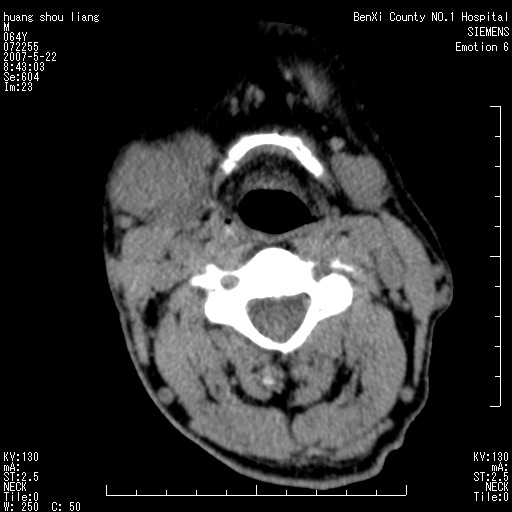

男性,64岁。颈部包块8年。最近增大。

对不起大家,可能是片子发太多有点乱,正常腮腺在下颌角的外侧,颌下腺在下颌体的中部内侧,本例在下颌角内侧偏下,和腺体一点关系都没有,从vrt和mpr上可以很明显看出来,再者肿块是好多粘连在一块的,大家在仔细看看,左侧可能也是吧,我还是考虑为肿大的淋巴结融合在一块,但性质??????

右侧腮腺下部均匀软组织密度肿块,外形不规则,与周围组织分界清晰,考虑右侧腮腺混合瘤或多形性腺瘤。

多考虑颌下腺混合瘤恶变,建议进一步检查,另外楼主重建图像很漂亮。

大家好,病理结果出来了,如大家所说,颌下腺混合瘤。

唉,解剖没学好吧,我诊断错了,不过还是有些不理解回去我在多看看书,谢谢大家的参与,以后我还会奉献好的病例。